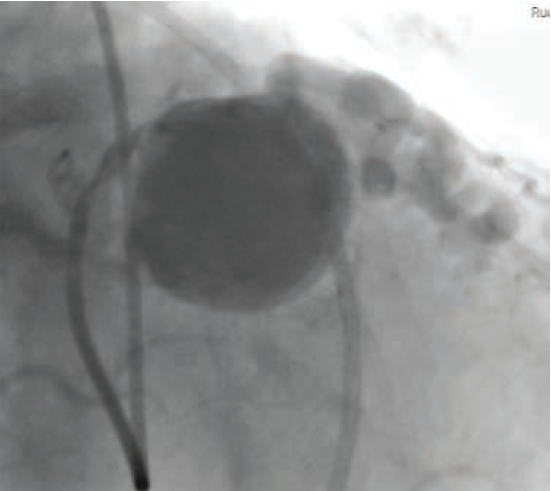

Cardiac catheterization revealed fistulae from the RCA to the pulmonary artery (PA) (Figure 2) and from the LAD to the PA, diffuse CAD, and a giant coronary artery aneurysm as previously described (Figure 3). The aneurysm demonstrated complex web-like vasculature extending towards the aortic root, across the right ventricular outflow tract, and into the proximal PA, with one large vessel connecting with the proximal RCA. The pulmonary-to-systemic flow ratio (Qp/Qs) was 1.14, indicating insignificant shunting, and cardiac index was normal.